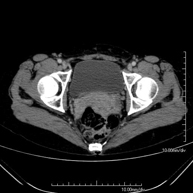

Prova diagnòstica que consisteix en obtenir imatges bi i tridimensionals de la pelvis d'alta definició anatòmica (estructures òssies, estructures vasculars, bufeta, úter i ovaris, pròstata i vesícules seminals, urèters, etc.) mitjançant l'ús d'un equip de TC (Tomografia Computeritzada). La majoria d'estudis requereixen l'ús de contrast iodat. - TC Abdominopèlvic

Exploració radiològica que mitjançant un sistema de raigs X i detectors que giren al voltant del pacient i que reconstrueixen les imatges per ordinador (TC Multidetector), permet l'estudi detallat dels ossos, els músculs i les articulacions de la pelvis. - TC de malucs